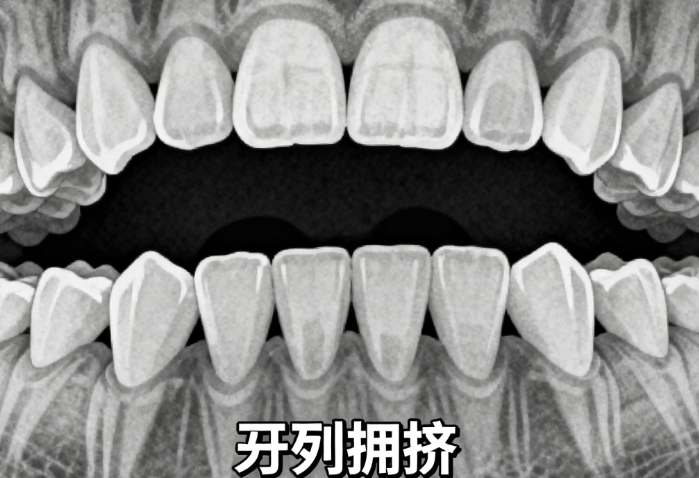

1. 上颌牙齿存在轻度拥挤或扭转,而下颌牙齿排列正常。例如:仅上颌前牙轻微前突(龅牙)或个别牙齿旋转,且下颌牙齿咬合关系稳定。